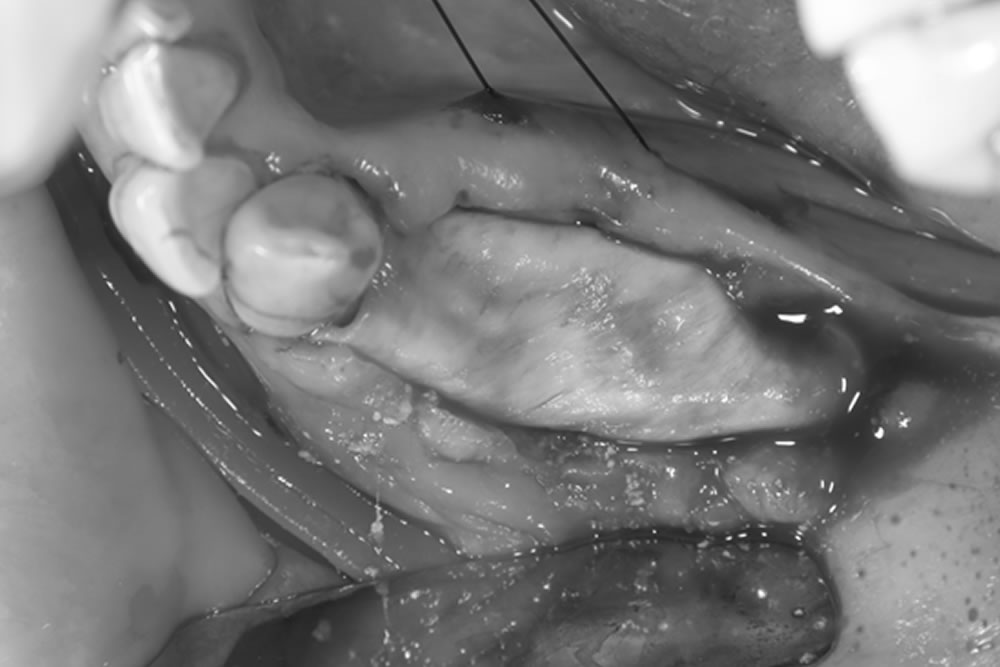

FGG(遊離歯肉移植術)の実施

移植した歯肉が安定して固定・生着できるよう、受容床を適切に形成します。

上顎の口蓋(上顎の内側)から、歯肉の移植片を慎重に採取します。

移植片が適切な位置で生着できるよう、受容床に密着させた状態で縫合し、しっかりと固定します。